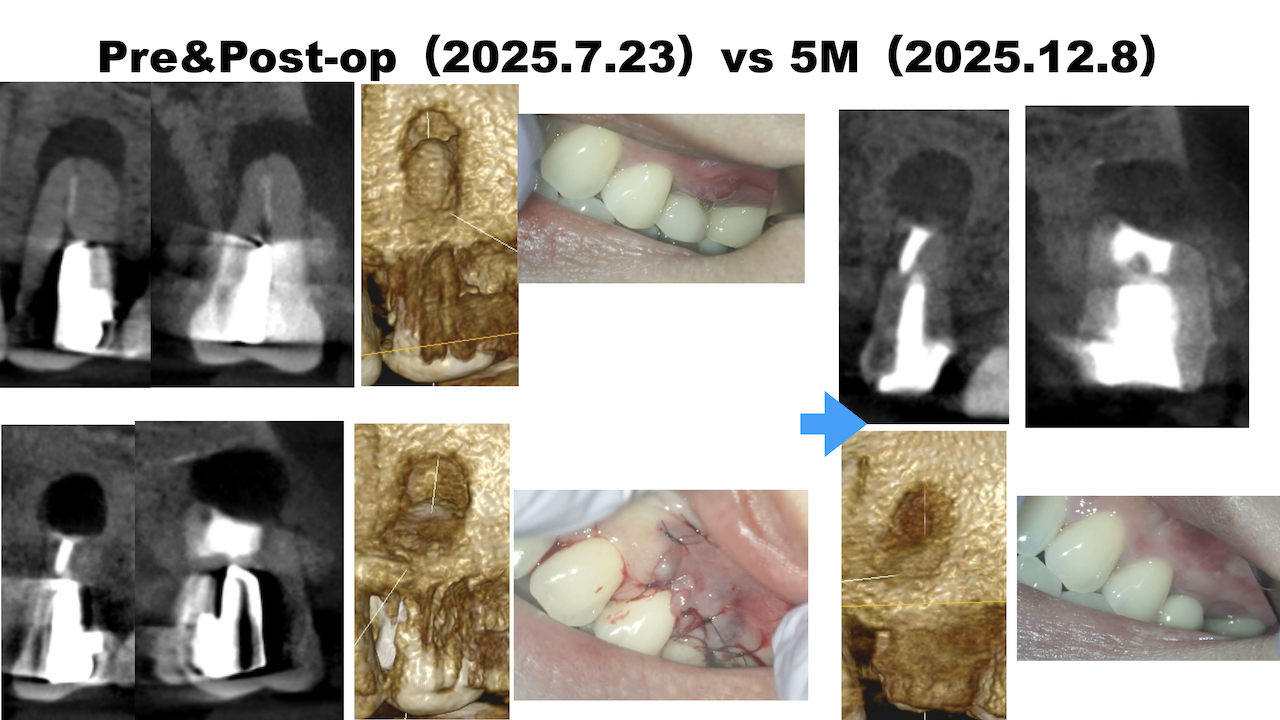

#13 Apicoectomy 5M recall(2025.12.8)

初診時と比較した。

劇的に歯槽骨が回復している。

治療前・直後と5ヶ月後を比較した。